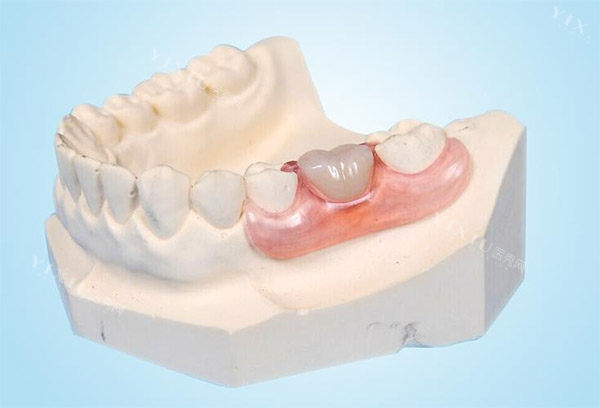

二、镶牙的优势与局限

优点:

操作简单:镶牙的过程相对简单,不需要进行复杂的手术,适合大多数患者。

费用较低:相比种植牙,镶牙的费用较为经济,适合预算有限的患者。

即刻使用:镶牙可以在短时间内完成,患者能够快速修复咀嚼功能和美观。

适应范围广:镶牙适用于多种缺牙情况,包括单颗牙齿缺失和全口无牙。

缺点:

稳定性差:镶牙的稳定性相对较差,尤其是活动假牙,可能会出现松动或脱落的情况。

影响邻牙:固定假牙需要磨损邻近的健康牙齿,可能会对其造成损害。

使用寿命短:镶牙的使用寿命通常较短,一般需要每隔5-8年更换一次。

舒适度差:镶牙可能会给患者带来不适感,影响日常饮食。